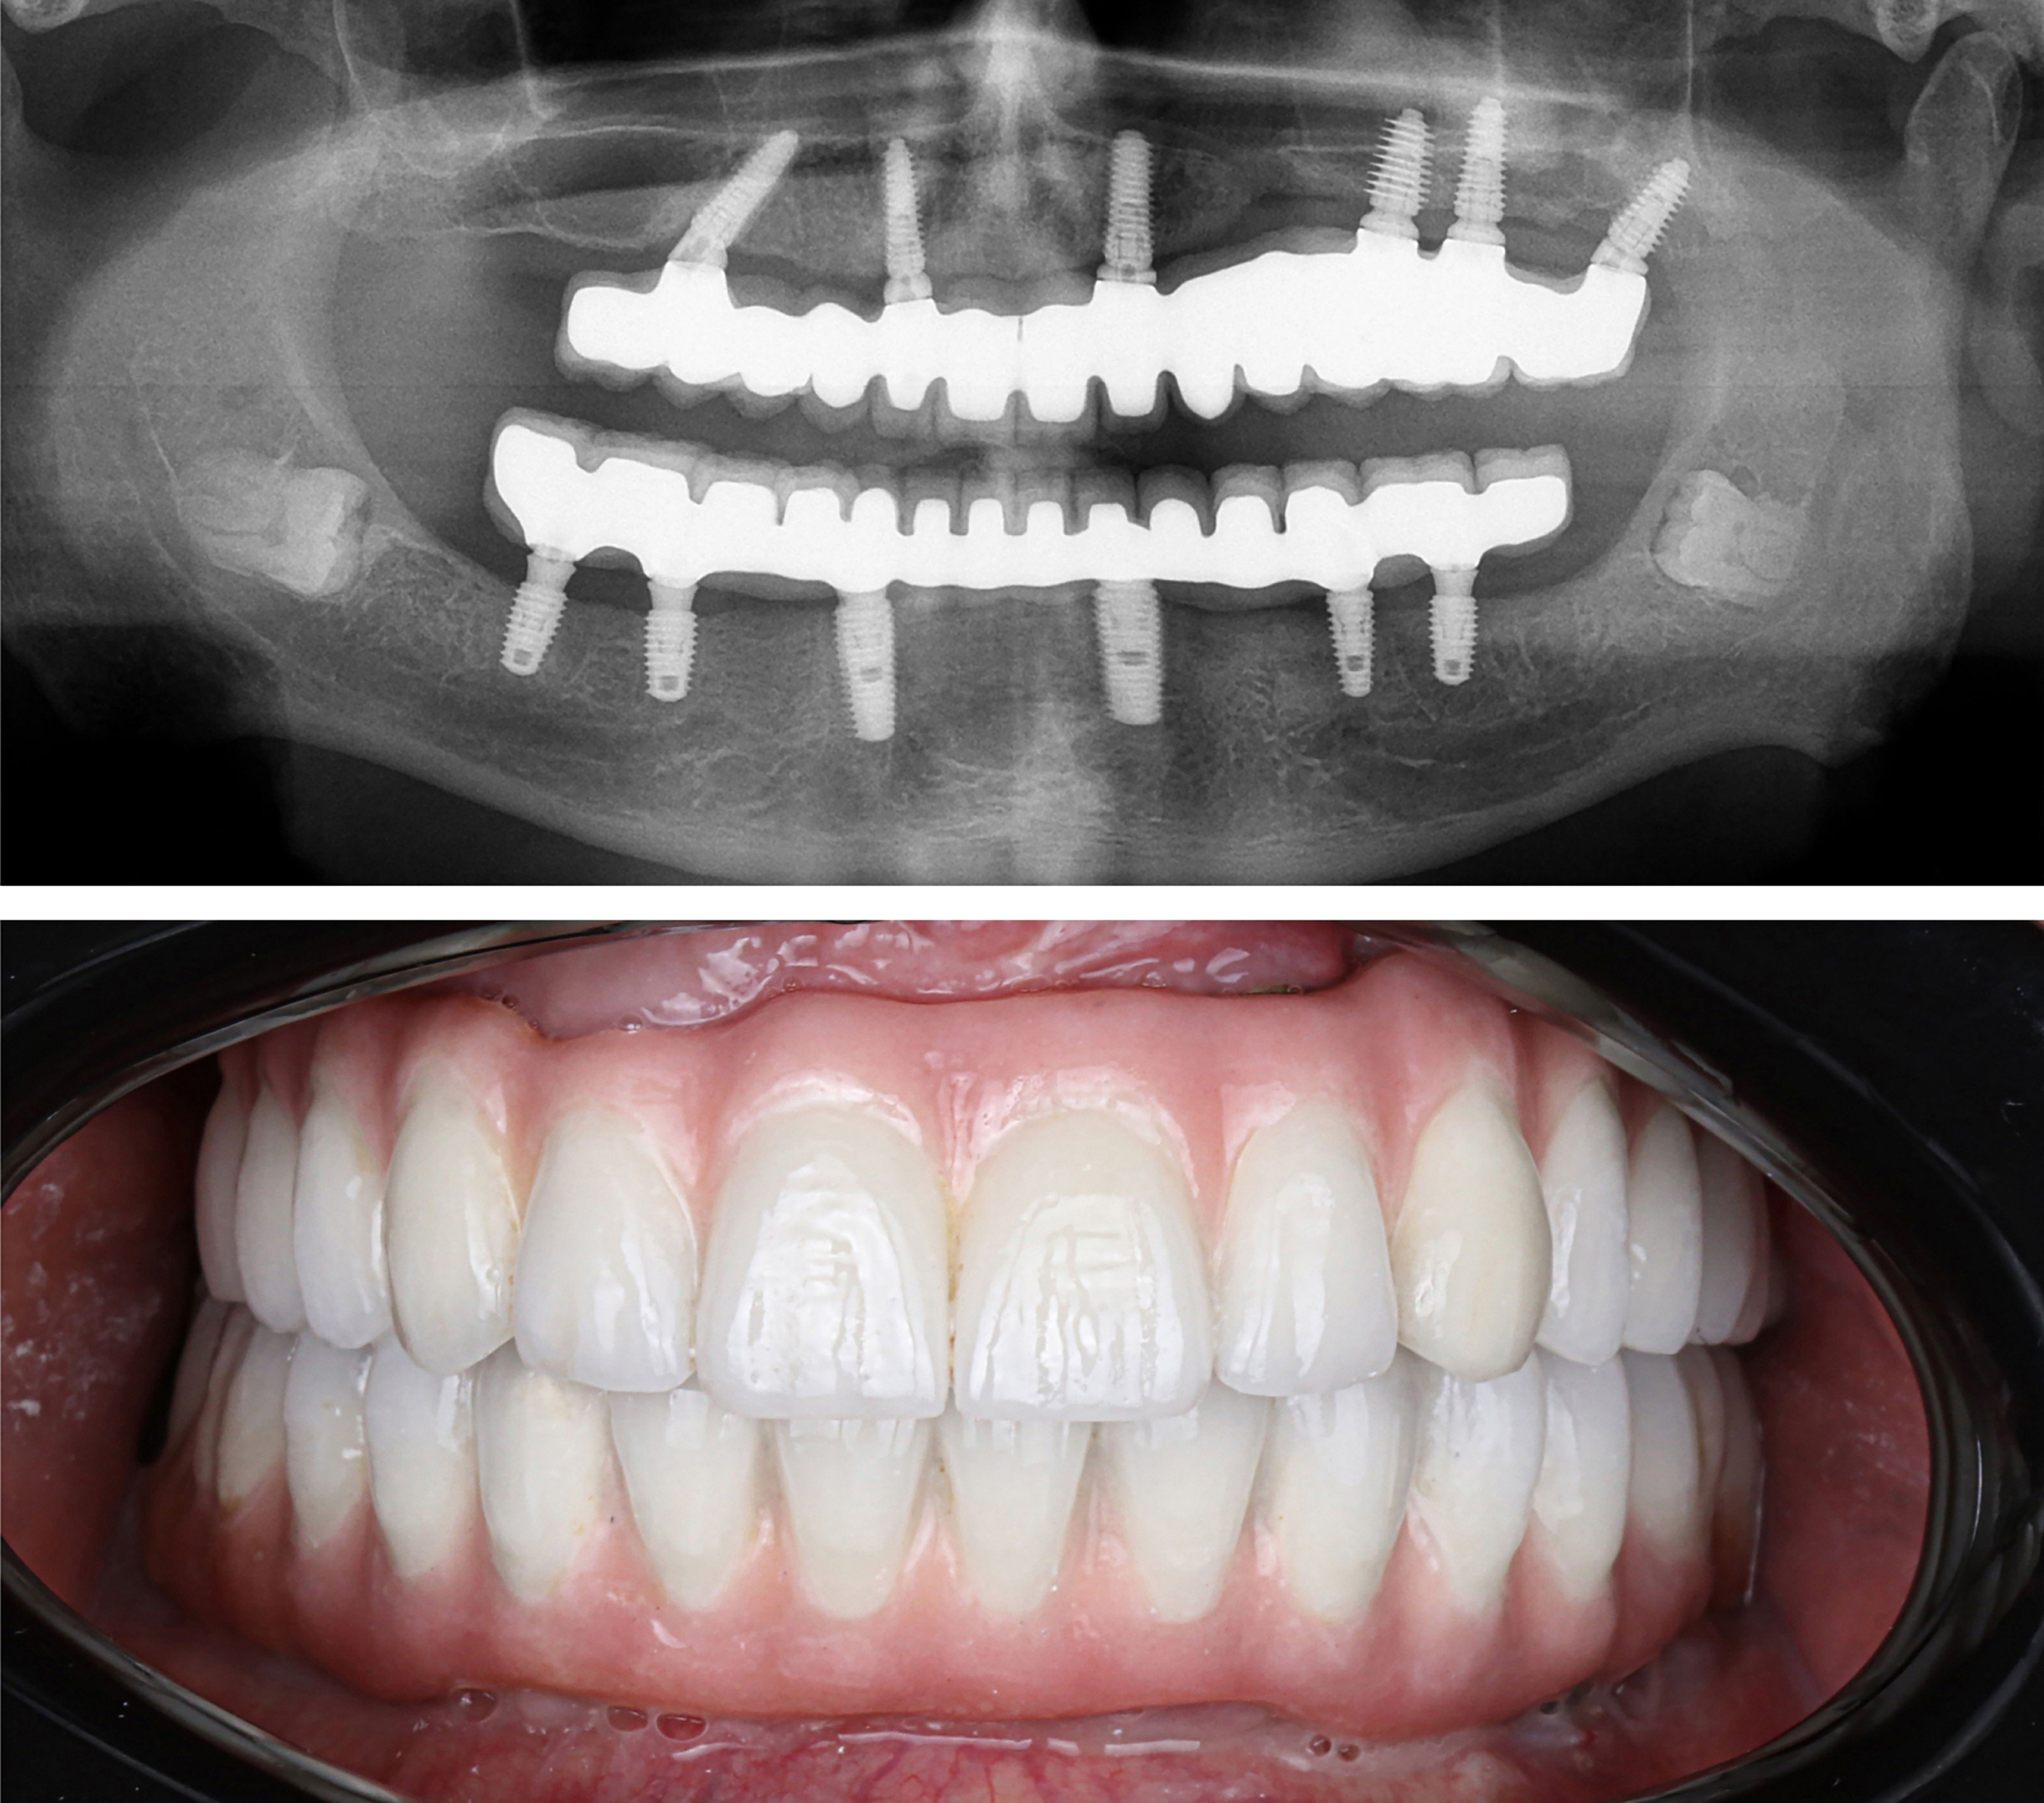

Example transformations achievable with dental implants

Starts as low as $9,999. Can Be Financed $175/mo*

We offer financing as far out as 144 months.

Credit score must be at least 600 to qualify for financing.

Includes everything from start to finish. No hidden fees.

Includes IV sedation. ($2500 Value)

Includes extraction of all remaining damaged teeth. ($4000 Value)

Includes surgical placement of 4 implants.

Includes bone grafting.

Includes final aesthetic fixed teeth.

** We offer affordable 3rd party financing up to 120 months. Monthly rate depends on approval.